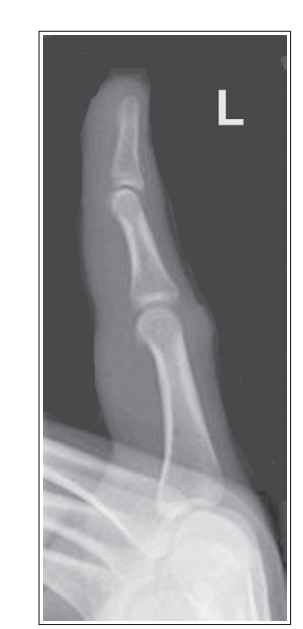

Foreshortening of distal phalanx

Finger was not flexed

What’s wrong with this oblique finger projection?

More than 45 degrees obliquity

Over-rotation